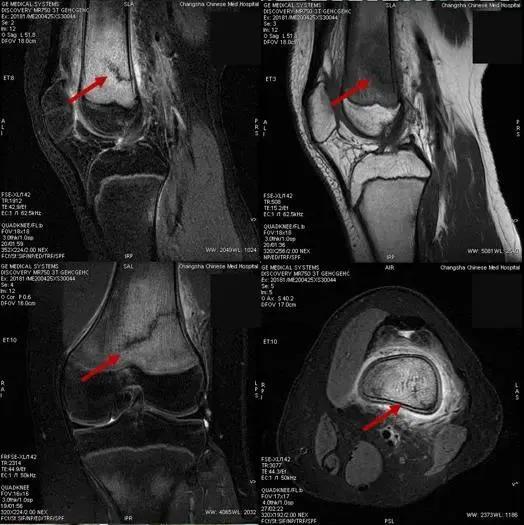

李政介绍,骨折一般分为创伤性骨折和病理性骨折两大类,应力性骨折又称“疲劳性骨折”,属于创伤性骨折一类,也可以说是“报复性”运动损伤,既因为长时间不运动或运动量较少,突然增加超运动量或短期内增加大量的运动,肌肉耐力超过极限,肌肉协调能力下降,保护能力减弱,使部分肌肉、韧带损伤,而此时运动应力易集中某段骨骼,造成所谓的“应力性骨折”或“疲劳性骨折”,长期减少运动本身也易使骨骼的韧性、强度减弱。应力性骨折通过普通X线片往往无法发现问题,容易发生漏诊,需要结合病史、查体,并配合磁共振检查来确诊诊断。